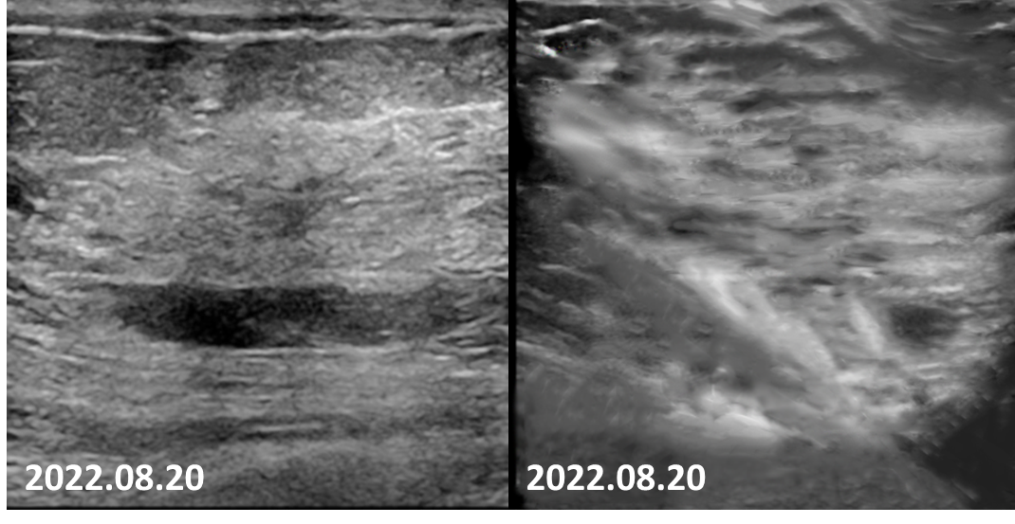

2022-08-20乳腺超声:左乳可见多处低回声结节,较大者位于12点钟,大小约11mm×7mm×11mm,距体表10mm,距乳头35mm,形态不规则,边缘成角,内回声不均匀。CDFI:内可及点状血流信号。左侧腋窝可见数个淋巴结回声,髓质消失,较大者大小约12mm×8mm。CDFI:内可见点状血流信号。右侧腋窝及双侧锁骨上窝未见明显肿大淋巴结。

图8 4疗程后,患者左乳肿物核心基本消失,淋巴结缩小至正常大小。